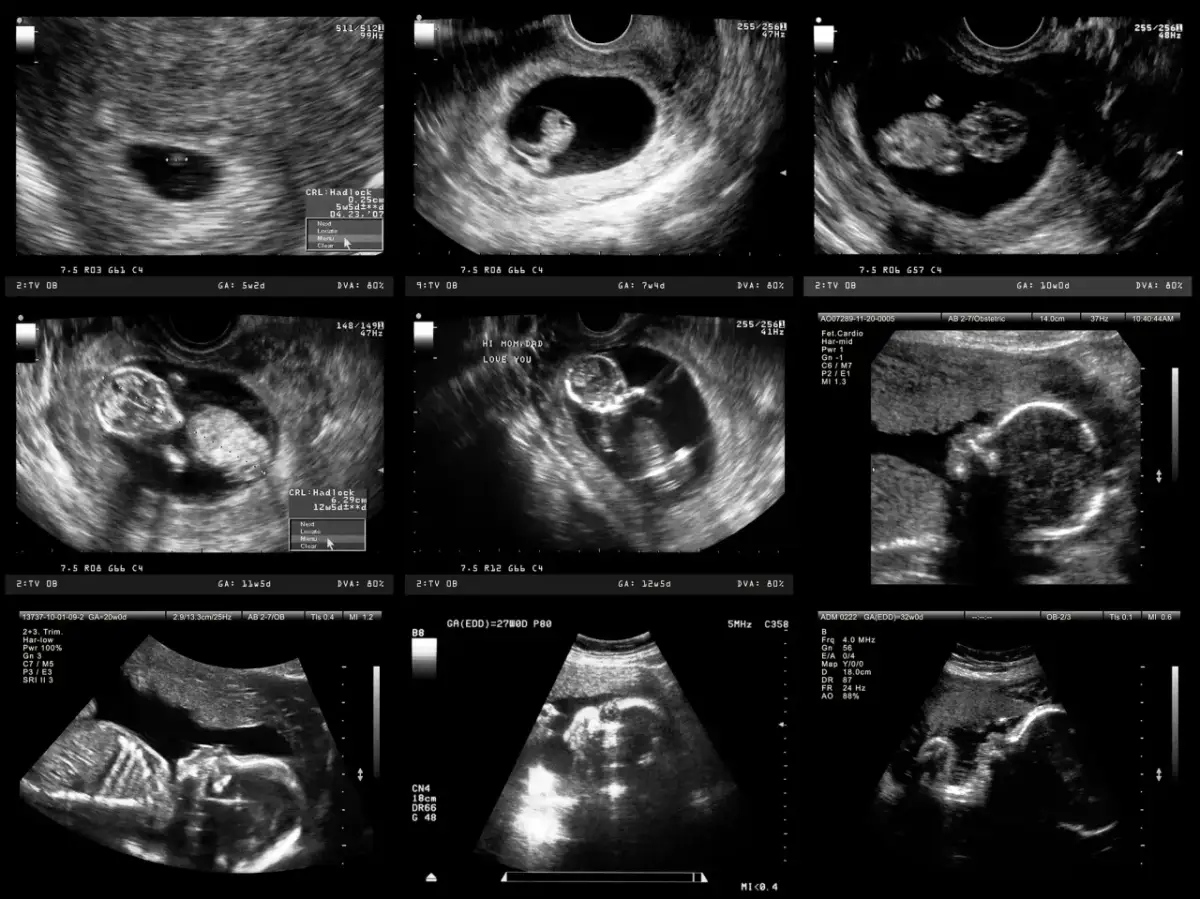

Badania prenatalne w 12. tygodniu ciąży to klucz do wczesnej oceny zdrowia dziecka.

- Badania przesiewowe I trymestru (USG genetyczne i test PAPP-A) odbywają się między 11+0 a 13+6 tygodniem ciąży.

- USG genetyczne ocenia markery wad genetycznych, takie jak przezierność karkowa (NT) i kość nosowa (NB).

Okres między 11+0 a 13+6 tygodniem ciąży nie jest wybrany przypadkowo na przeprowadzenie badań przesiewowych I trymestru. To właśnie w tym czasie płód osiąga odpowiedni rozwój, który pozwala na precyzyjną ocenę kluczowych parametrów. Wcześniej niektóre struktury są zbyt małe, aby je dokładnie zmierzyć, a później, po 14. tygodniu, pewne markery, takie jak przezierność karkowa, mogą ulec zmianie lub zaniknąć, co znacząco obniżyłoby wiarygodność badania. Dlatego tak ważne jest, aby nie przegapić tego okna czasowego.

Badania prenatalne I trymestru, czyli USG genetyczne i test PAPP-A, to nie tylko rutynowa kontrola. To kompleksowa ocena, która pozwala na wczesne oszacowanie ryzyka wystąpienia najczęstszych wad genetycznych, takich jak zespół Downa (trisomia 21), zespół Edwardsa (trisomia 18) czy zespół Patau (trisomia 13). Co więcej, podczas USG lekarz może również zwrócić uwagę na pewne markery, które mogą wskazywać na zwiększone ryzyko wad serca lub innych nieprawidłowości rozwojowych. Dzięki temu zyskujemy cenną wiedzę na bardzo wczesnym etapie ciąży.

USG genetyczne to bez wątpienia jedno z najważniejszych badań w całej ciąży. Jest to szczegółowe badanie ultrasonograficzne, które trwa zazwyczaj około 20-30 minut i jest wykonywane najczęściej przez powłoki brzuszne. W niektórych przypadkach, zwłaszcza gdy widoczność jest utrudniona, lekarz może zdecydować o wykonaniu badania dopochwowego. Niezależnie od metody, jest to badanie nieinwazyjne i całkowicie bezpieczne zarówno dla Ciebie, jak i dla Twojego dziecka.

Przezierność karkowa (NT): Co oznacza ten tajemniczy wskaźnik na ekranie USG?

Jednym z kluczowych parametrów ocenianych podczas USG genetycznego jest przezierność karkowa (NT). To pomiar zbiorniczka z płynem, który gromadzi się na karku płodu. W 12. tygodniu ciąży norma dla tego wskaźnika wynosi do 2,5 mm. Wartość podwyższona, czyli powyżej normy, może wskazywać na zwiększone ryzyko wystąpienia wad genetycznych, takich jak zespół Downa, Edwardsa czy Patau, a także niektórych wad serca. Należy jednak pamiętać, że podwyższone NT to jedynie marker ryzyka, a nie diagnoza wady. Wiele dzieci z nieco podwyższonym NT rodzi się całkowicie zdrowych.

Obecność kości nosowej (NB): Dlaczego lekarz zwraca na nią szczególną uwagę?

Kolejnym ważnym markerem, na który lekarz zwraca szczególną uwagę, jest obecność kości nosowej (NB). Brak lub hipoplazja (niedorozwój) kości nosowej jest kolejnym, silnym wskaźnikiem zwiększonego ryzyka zespołu Downa. U płodów z zespołem Downa kość nosowa jest często niewidoczna lub znacznie mniejsza niż u płodów zdrowych. Dlatego tak istotne jest, aby lekarz dokładnie ocenił ten parametr podczas badania.

Poza przeziernością karkową i kością nosową, lekarz podczas USG genetycznego dokonuje bardzo szczegółowej oceny ogólnej anatomii płodu. Sprawdza ciągłość powłok brzusznych, budowę czaszki, obecność i prawidłowy rozwój kończyn. Ocenia również czynność serca płodu, licząc uderzenia i zwracając uwagę na jego rytm. Ponadto, analizuje przepływy krwi w przewodzie żylnym (DV) i zastawce trójdzielnej (TR). Nieprawidłowe przepływy w tych naczyniach mogą być dodatkowymi markerami wad genetycznych lub serca. To wszystko składa się na kompleksowy obraz zdrowia Twojego dziecka na tym wczesnym etapie.